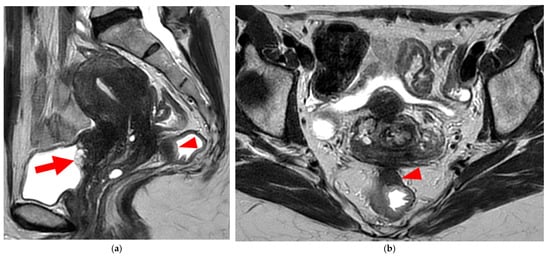

A type 5B USL (Figure 7) is nodular with spiculated margins. A type 5B USL may also display an isolated nodule with microcystic content.

Figure 7. Pelvic MRI scans of two patients with HTD type 5B USLs. (a) Patient 1: sagittal T2WI shows a microcystic nodule (arrow) within the origin of the right USL (arrowhead). (b,c) Patient 2: axial (b) and sagittal (c) T2WI show a nodular left USL with spiculated margins (arrow) and a right ovarian endometrioma (arrowhead).